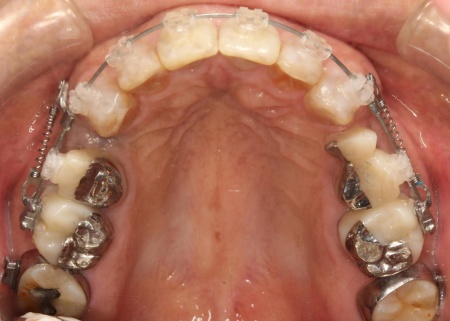

まずは、口腔内全体の矯正治療から開始します。

上顎は左上の歯が欠損していたため、左右のバランスを整える目的で、右上の歯(第1小臼歯)を抜きました。

その後、ワイヤー矯正とクローズドコイル(バネの装置)を使ったスピード矯正を行い、前歯を後方に移動させます。

下顎は残根も利用しながら、矯正用の小さなネジ「テンポラリーインプラント(インプラントアンカー)」を顎の骨に埋め込んで固定源とする方法も併用し、歯を移動させました。

矯正期間中は定期的に装置の調整を行い、歯の動きや噛み合わせの変化を確認しながら治療を進めています。

矯正期間終了後は、被せ物による治療に移行します。

上顎の前歯2本ずつと奥歯4本(左右中切歯・第2小臼歯・第1大臼歯)、下顎の奥歯7本(左第1小臼歯・左右第2小臼歯・第1大臼歯・第2大臼歯)には、見た目が自然なセラミックの被せ物「ジルコニアクラウン」を装着しました。